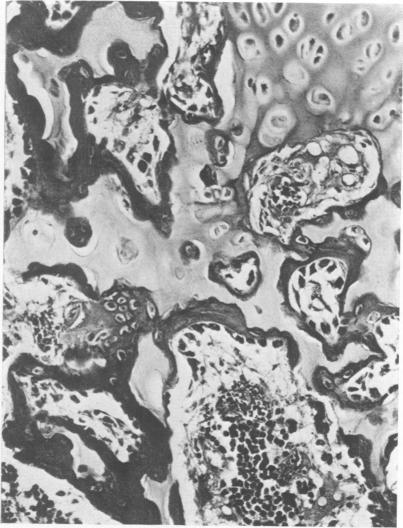

Disease in a large pig herd reared intensively and kept on sulfate-rich drinking water is described. It is the first report of diseased progeny of sows with high sulfate intake. Results of two surveys are presented, one for water with sulfate in excess of 2000 ppm and one for water with less than 1000 ppm. The management practices are described in detail. Disease of Survey I was manifested by high morbidity and mortality (50% of 600) in piglets, incoordination in piglets and some adult stock and osteopathy in piglets and weaners. In Survey II disease was less severe and restricted to piglets. Detailed histopathological studies revealed myelin deficiency in brain and spinal cord of sows and piglets, interferred endochondreal ossification of long bones of piglets and weaners, fatty changes of livers and interstitial nephritis in piglets and weaners. The changes in the nervous tissue were considered due to delayed fixation as tissue was only immersed in fixative and not perfused with it immediately after death. Similar changes have been described for pigs deficient in copper. Copper content of tissue and body fluids of pigs of this study were normal, as were the serum inorganic phosphate and total calcium levels. The bone changes observed have also been reported for rats given dextran sulfate injections, for pigs on experimental low-copper sulfate-enriched diet and for pigs reported low in copper and fed a diet supplemented with sulfide. The cause of the locomotor disturbance and mortality in piglets was not established.

描述了一个集约化饲养且饮用富含硫酸盐的饮用水的大型猪群中的疾病情况。这是关于高硫酸盐摄入量的母猪后代患病的首次报告。给出了两项调查结果,一项针对硫酸盐含量超过2000 ppm的水,另一项针对硫酸盐含量低于1000 ppm的水。详细描述了管理措施。调查I中的疾病表现为仔猪发病率和死亡率高(600头中有50%),仔猪和一些成年猪出现共济失调,仔猪和断奶仔猪出现骨病。调查II中的疾病较轻,仅局限于仔猪。详细的组织病理学研究显示,母猪和仔猪的脑和脊髓存在髓磷脂缺乏,仔猪和断奶仔猪的长骨软骨内骨化受到干扰,仔猪和断奶仔猪的肝脏出现脂肪变性和间质性肾炎。神经组织的变化被认为是由于固定延迟,因为组织只是浸泡在固定剂中,死后没有立即进行灌注固定。对于缺铜的猪也有类似变化的描述。本研究中猪的组织和体液中的铜含量正常,血清无机磷酸盐和总钙水平也正常。仔猪运动障碍和死亡的原因尚未确定。